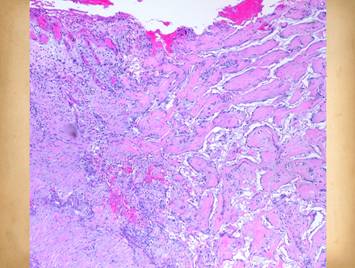

Left, patient with rheumatoid arthritis and Factor V Leiden hypercoagulable state.  After all usual care for this pathological ulcer, it remains edematous, hyperemic, inflamed, and not healing.  Application of Integra has completely subsided the inflammation.  In the bottom pane, the Integra reconstructed skin remains stable a year later.  (Disease flareup resulted in a similar situation on the posterior right ankle, seen as another piece of Integra over the achilles).  Right, patient with ulceration due to Protein S deficiency hypercoagulability.  The same pattern is seen, complete arrest of persistent refractory inflammation once the Integra is applied.  Center, histology of Integra 10 days after placement.  The few cells seen are “pioneer” and “transitional” cells that are the histogenetic precursors.  Never when Integra is placed on a properly prepared wound will acute inflammatory cells (neutrophils) appear.

Inflammation and its effects are suppressed.  Inflammation is the normal protective response to injury.  It also has a central role to initiate repair which arises as injury and inflammation subside.  However, inflammation is inherently destructive, and while it triggers wound repair, repair processes are suppressed or damaged by persistent acute inflammation.  Persistent acute inflammation is adverse to wound healing.  When inflammation occurs reactively for identifiable reasons, e.g. an infection or a fracture pseudarthrosis, then inflammation can be controlled by fixing the cause.  When inflammation  arises for erroneous reasons, e.g. Crohn’s or rheumatoid disease, then inflammation per se must be stopped.  For either scenario, until it is stopped, physiologic wound repair will remain suppressed, and surgical wound repair is prone to fail or even cause more damage (wound pathergy).  When Integra is applied to a wound, inflammation ceases.  The gag’s in the material hide the wound from platelets and leukocytes which aborts inflammation.  They also allow the material to be recognized as self, inviting histogenesis by pioneer stem cells which will find the matrix.  Observed histologically, there are never inflammatory cell infiltrates in the matrix nor even leukocyte concentration in subjacent host.  Clinical signs of inflammation are suppressed or eliminated.  Pain is often conspicuously absent after Integra, and any pre-operative periwound erythema and edema abate rapidly (left upper images).